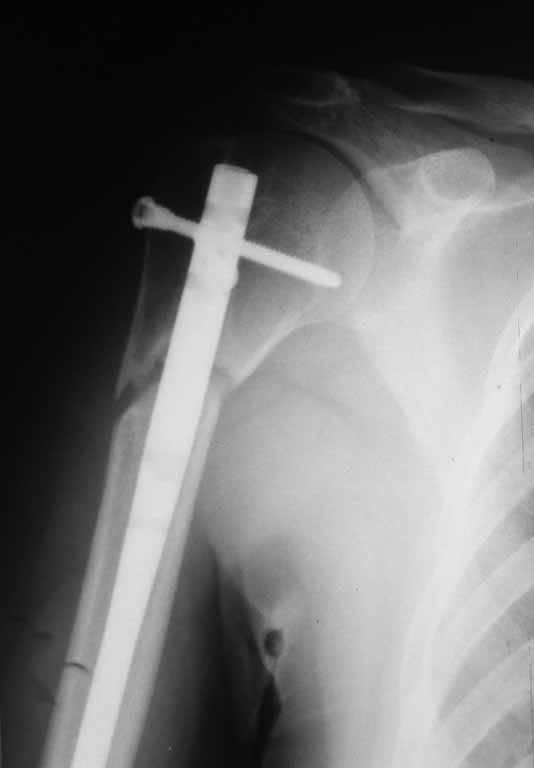

Уважаемые коллеги представляю вашему вниманию пациентку 27 лет с ложным суставом

проксимального отдела плечевой кости в условиях БИОС.

Травма 11 мес. назад в результате падения. У нас в клинике на 2-е сутки выполнена закрытая

репозиция, БИОС плечевой кости. Послеоперационный период протекал без осложнений. После

выписки наблюдалась в ЦРБ по м\ж. Спустя такое большое количество времени направлена к нам

для контрольного осмотра с жалобами на умеренный болевой синдром. На контрольных

рентгенограммах имеются признаки ложного сустава проксимального отдела плечевой кости.

Пациентка запланирована на госпитализацию.

Прошу совета в тактике оперативного лечения.

Видим следующие возможные варианты:

1.Выполнить динамизацию штифта, но смущают большие

сроки после операции и конечность верхняя (не опорная )

2.Произвести удаление металлоконструкции и экстракортикальный реостеосинтез с костной аутопластикой

Буду признателен за ваши советы и мнение.